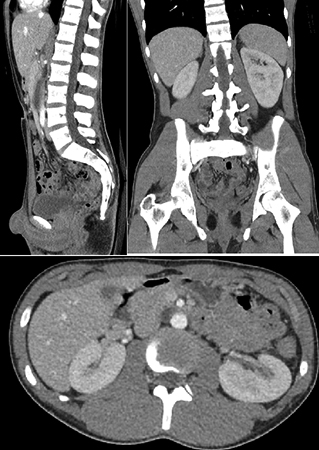

Компьютерная томография (КТ)

Хронологически первым излучением, позволяющим строить изображение внутренних тканей без их разрушения, стали рентгеновские лучи. Эти лучи по-разному проникают сквозь мягкие и твердые части тела, что позволяет построить на экране ясные очертания.

Однако, обычный рентгеновский снимок дает изображение сканируемых тканей «наложенными» друг на друга. Томография же дает именно «срезы», на которых отображаемые ткани не создают накладок, и могут быть видны по отдельности. Для построения такого изображения производится ряд снимков с разных точек. Как правило, исследуемый объект помещается в сканер, а рентгеновская камера вращается вокруг него, делая серию необходимых снимков. И далее, по полученным снимкам компьютер томографа строит изображение срезов – точно так же, как инженер по нескольким проекциям чертежа может построить любое сечение детали.

Именно поэтому такая томография стала называться «компьютерной». Строго говоря, в любом томографе присутствует компьютерная обработка, однако, исторически сложилось так, что термином «компьютерная томография» обозначается именно рентгеновская томография. В последних моделях таких томографов сканирующая головка не просто вращается вокруг исследуемого органа по кругу, а описывает спираль, что позволяет построить не один, а сразу много срезов на каждом витке спирали. Такая томография называется «спиральной» (СКТ).

Вред компьютерной томографии

Компьютерная томография, с точки зрения воздействия на организм, по сути, является обычным рентгеновским аппаратом, делающим ряд снимков. И вредные стороны компьютерной томографии схожи с вредными сторонами рентгена. Безусловно, в современных томографах применен ряд технологий, позволяющих снизить лучевую нагрузку на организм, однако, полностью исключить ее невозможно в принципе. А проникающее излучение способно вступать в реакцию с молекулами, составляющими организм человека. В результате таких реакций происходит целый ряд негативных явлений:

Поскольку небольшое количество рентгеновских лучей всегда имеется вокруг нас – природа позаботилась, чтобы организм мог справиться с результатами воздействия этого небольшого количества лучей самостоятельно. Однако, рентген и томография излучают гораздо сильнее, чем обычный природный фон. Для сравнения – годовая доза облучения от природного фона в организме человека составляет 5-20 мЗв (зиверт – единица полученной дозы излучения). А одно томографическое исследование дает дозу 2-15 мЗв, в зависимости от продолжительности и от сканируемого органа. Поэтому этими видами исследований недопустимо злоупотреблять, и применять их необходимо исключительно по необходимости.

Дело в том, что, как было указано выше, в описаниях методик, КТ-томография позволяет хорошо различить структуру твердых тканей организма, и гораздо хуже отображает состояние мягких. МРТ же, гораздо лучше подходит для исследования мягких тканей, и меньше подходит для исследования твердых.

Доза облучения составляет около 10 мЗв, что приравнивается к 40 месяцам естественного облучения. Это довольно высокая доза, потенциально способная повысить риск развития рака печени, поджелудочной железы, почек и других органов брюшной полости и малого таза.